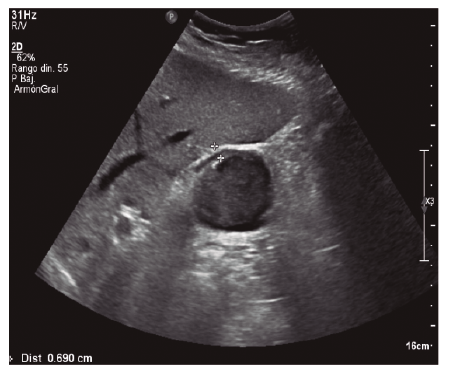

Presentamos el caso de un paciente que sufre un traumatismo abdominal cerrado por coz de caballo observándose en pruebas de imagen engrosamiento de la pared de la vesícula biliar con contenido hemorrágico como único hallazgo, sin otras lesiones asociadas intraabdominales.

Paciente de 38 años sin antecedentes personales de interés que acude a Urgencias por traumatismo abdominal cerrado por coz de caballo. A su llegada a nuestro Centro se encuentra estable hemodinamicamente. A la exploración destaca dolor a la palpación en hipocondrio derecho sin signos de irritación peritoneal. Se solicita analítica en la que destaca cifra de hemoglobina de 11,9 g/dL y transaminasas levemente elevadas, no constaban analíticas previas. Ante la estabilidad del paciente se solicita ecografía (Figuras 1 y 2) que se completa con TAC (Figura 3).